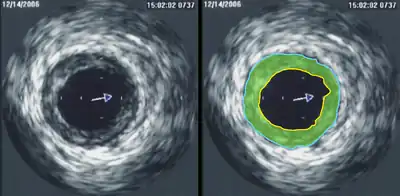

Intravascular ultrasound

Intravascular ultrasound (IVUS) is a specialized form of echocardiography that uses a catheter to insert the ultrasound probe inside blood vessels. This is commonly used to measure the size of blood vessels and to measure the internal diameter of the blood vessel. For example, this can be used in a coronary angiogram to assess the narrowing of the coronary artery. If the catheter is retraced in a controlled manner, then an internal map can be generated to see the contour of the vessel and its branches.